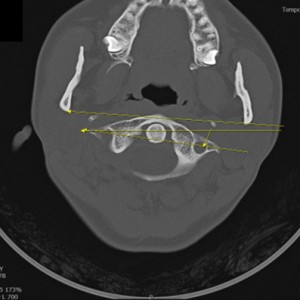

안면 두개골 엑스레이 검사

Submento Vertex View 포함

안면 두개골 CT

경추 1,2번의 변위 파악

턱의 소리가 오래되지 않아서 근육의 긴장만 있는 경우 치료 후 소리의 감소가 빠른 편이나 인대의 문제일 경우 턱의 위치를 교정후 인대를 강화하는 치료를 추가적으로 해서 더 줄일수 있습니다. 디스크가 닳아버린 문제라면 치료후에도 소리가 남을수 있습니다. CT와 초음파등의 영상진단을 통해 치료 예후와 경과를 확인 가능합니다.